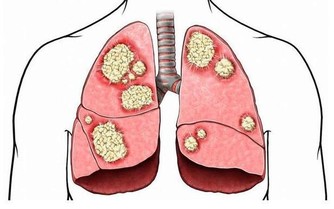

此時,即使身體尚未出現明顯的不適,已是物質依賴型酒癮患者,建議此類人應考慮戒酒並進行治療。 酒癮遺傳:爸爸是酒鬼孩子智商低 男士酗酒不但影響自身健康,還有可能把酒癮傳給下一代。因為丈夫如果大量喝酒。 即使是啤酒,妻子懷孕後生下的孩子可能就是「嬰兒酒綜合徵」患者。 這樣的孩子愛哭鬧、智力弱,長大後也易酒精成癮。由於爸爸常在周末喝得醉醺醺的,因此美國將這樣的孩子稱為「星期天嬰兒」。 希望通過這些內容介紹,每個男性都能夠警惕,當你貪圖酒精給你帶來快樂的時候。 可是你卻也是在危害你今後的孩子,所以男性健康專家希望每個男性,應該盡量減少喝酒酗酒的行為。 精子的質量很重要,高質量的精子產出優質的後代,那麼男人精子在什麼時候的質量為最高呢? 有研究發現,男人最佳的生育年齡是三十歲,當然這也只是相對而言的。 如今有許多六十歲甚至更高年齡的男性所生的孩子一樣很正常,所以也不能一概而論了。 為什麼說男人在三十歲時是最佳的生育年齡呢? 之所以男性到三十歲才被定會最佳的生育年齡,是通過男性的生長發育相對女性較晚,性成熟時間延後,體力、經歷達到巔峰時期也相對較晚。 Advertisement